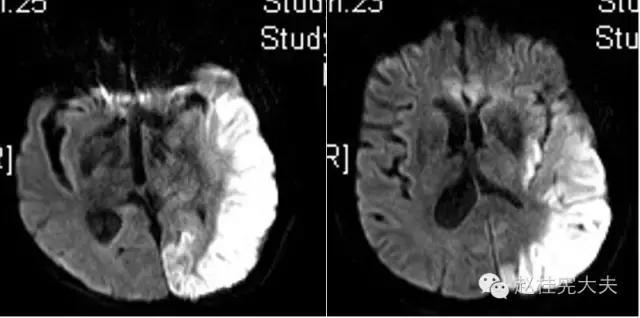

上周,于发病后2月复查磁共振:

到此为止,MELAS的诊断应该在没有基因确诊的情况下在临床上得到认可了,患者明确诊断为线粒体脑肌病伴乳酸血症和卒中样发作(MELAS),解释了患者的所有症状,患者母亲不明原因地死亡也得以真相大白,患者的相关亲属们在未来的人生路上也多了一份呵护......